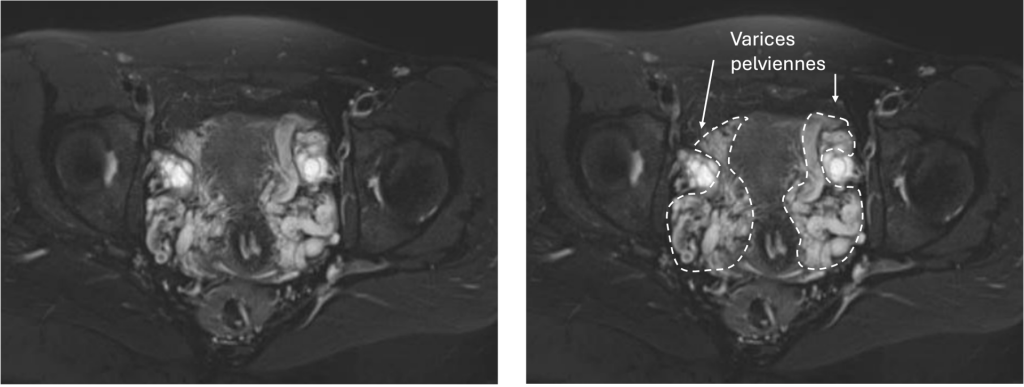

Quels examens permettent de diagnostiquer des varices pelviennes ?

Différents examens permettent de faire le diagnostic de varices pelviennes et d’exclure d’autres pathologies comme les fibromes ou l’adénomyose

IRM pelvienne : examen de référence, très précis pour évaluer l’extension et la sévérité des varices.